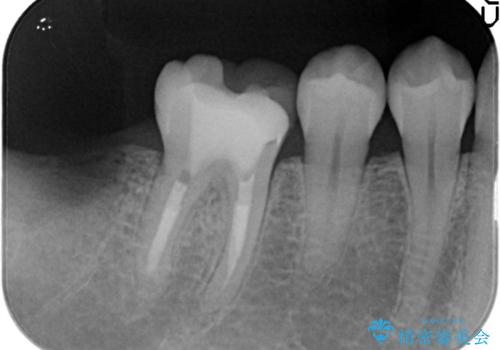

- 奥歯が痛いことを主訴に来院されました。

根管治療を行なったのちオールセラミッククラウンにて修復補綴を行いました。